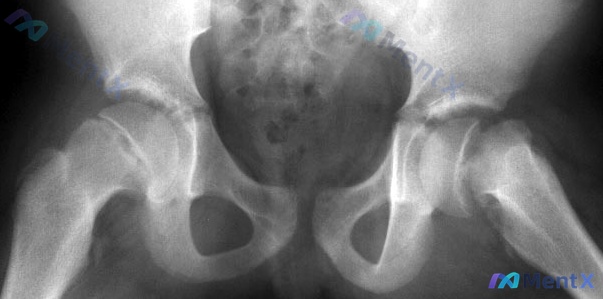

看到一道挺经典的骨科生物力学选择题,刚好结合资料整理一下思路。 题目是:对于下列哪一个数字(影像),股骨粗隆间外翻截骨加刀片板固定是最合适的治疗方法? --- 先把关键逻辑拆解一下,这题其实不是考“有没有骨折”,而是考“力学环境”。 1. 核心术式的目的是什么? 股骨转子间外翻截骨术(VITO)+...